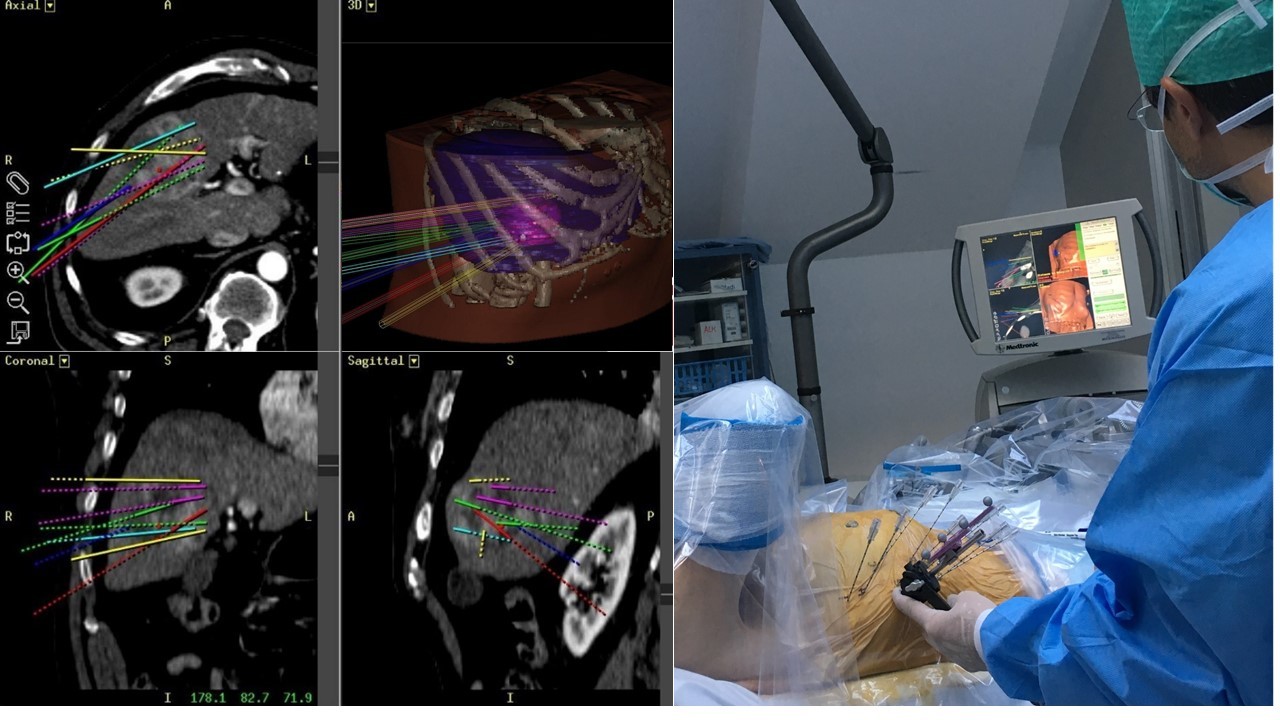

In 2001 we performed the first in man "stereotactic radiofrequency ablation (SRFA)" of a liver tumor 1 by introducing the stereotactic planning, image fusion and guidance principles into the field of thermal ablation. In contrast to the conventional "freehand" single-probe technique multiple probe positions are planned on 3D image datasets in order to cover the tumor by overlapping ablation zones. The whole procedure is performed under general anesthesia using muscle paralysis and respiratory triggering. An optical navigation system is used to adjust an aiming device for precise coaxial needle placement. Up to three radiofrequency electrodes are introduced through the coaxial needles for serial tumor ablation. Immediate fusion of the post ablation contrast-enhanced CT with the planning CT allows for rapid reliable intraoperative assessment of the result.

Figure 1A: Breast cancer liver metastasis with 9 cm in left liver lobe.

Figure 1B: Control CT with 15 coaxial needles in place.